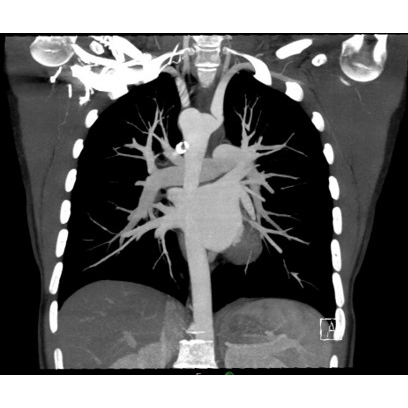

CT angiogram chest: Mild tracheal narrowing associated with a vascular ring and a right aortic arch Case Photo #2 Case Photo #3 .